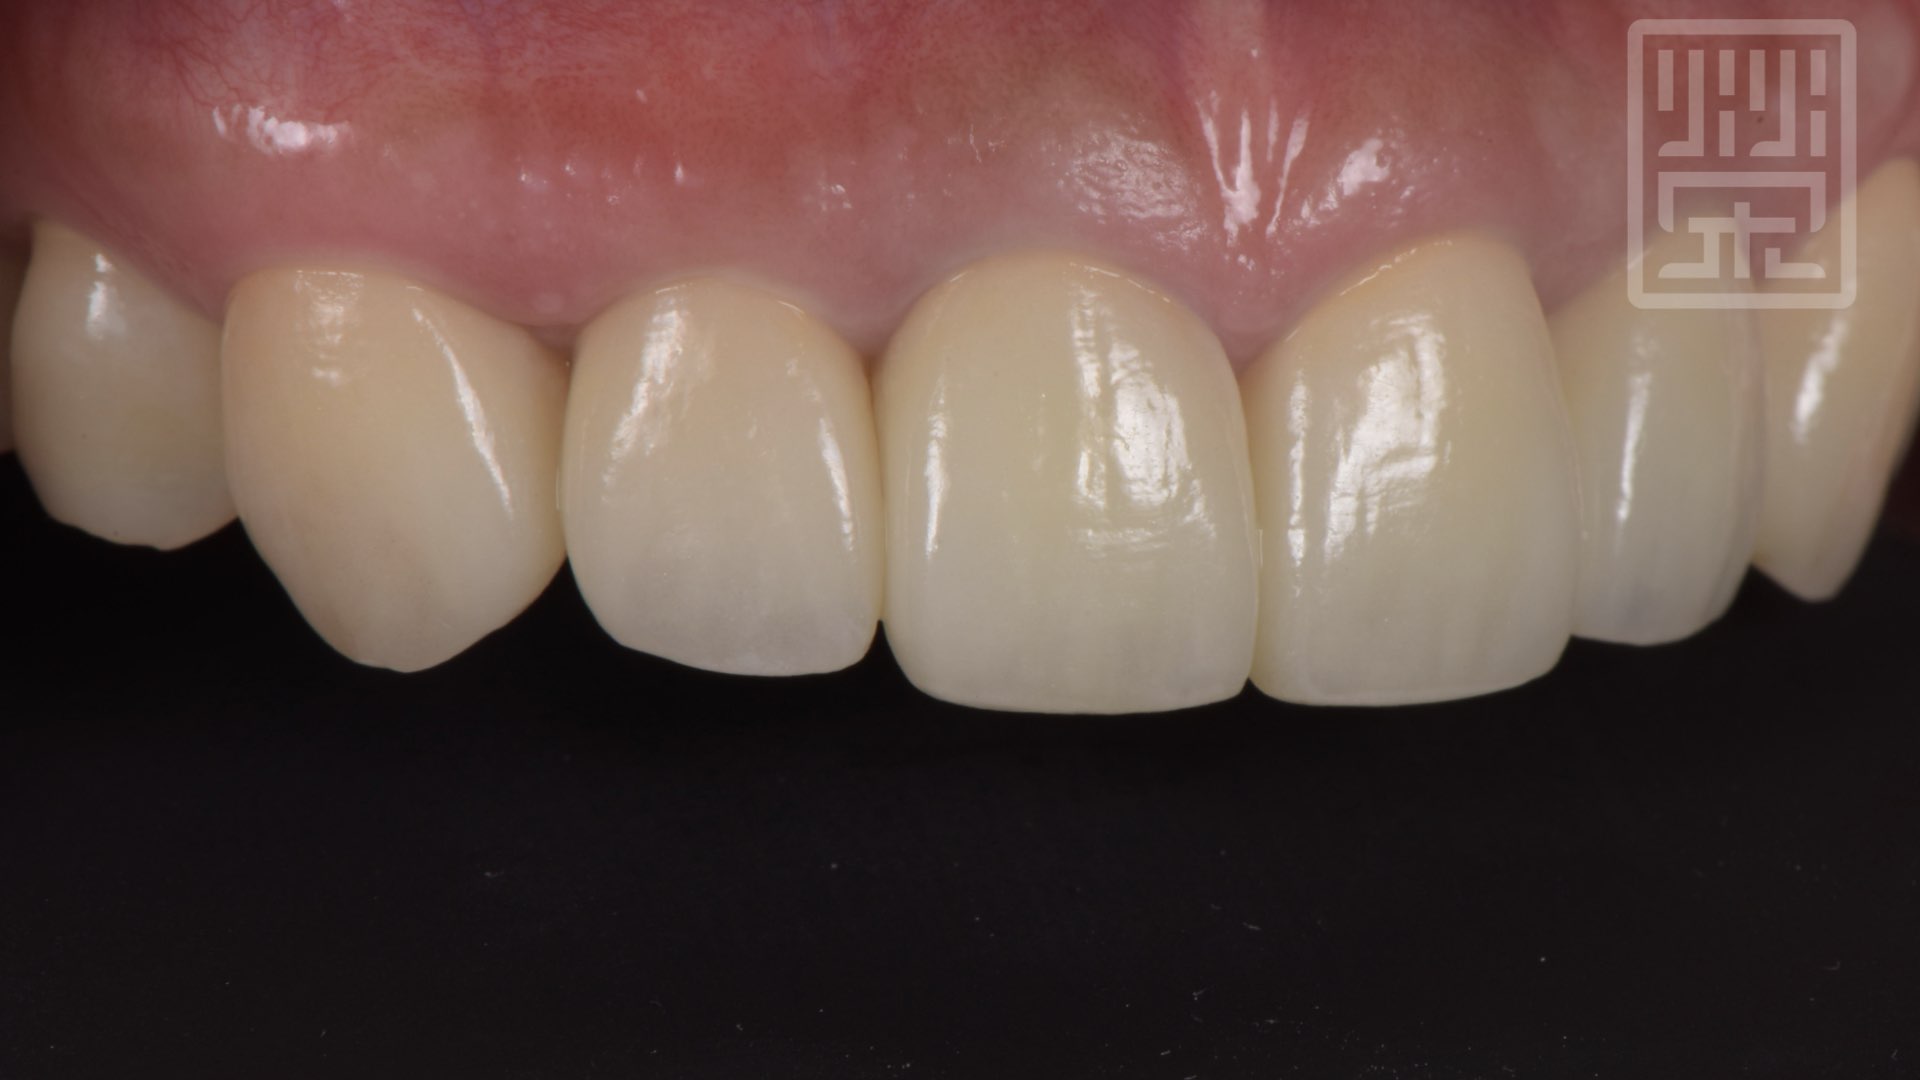

保護性咬合

保護性咬合痕跡